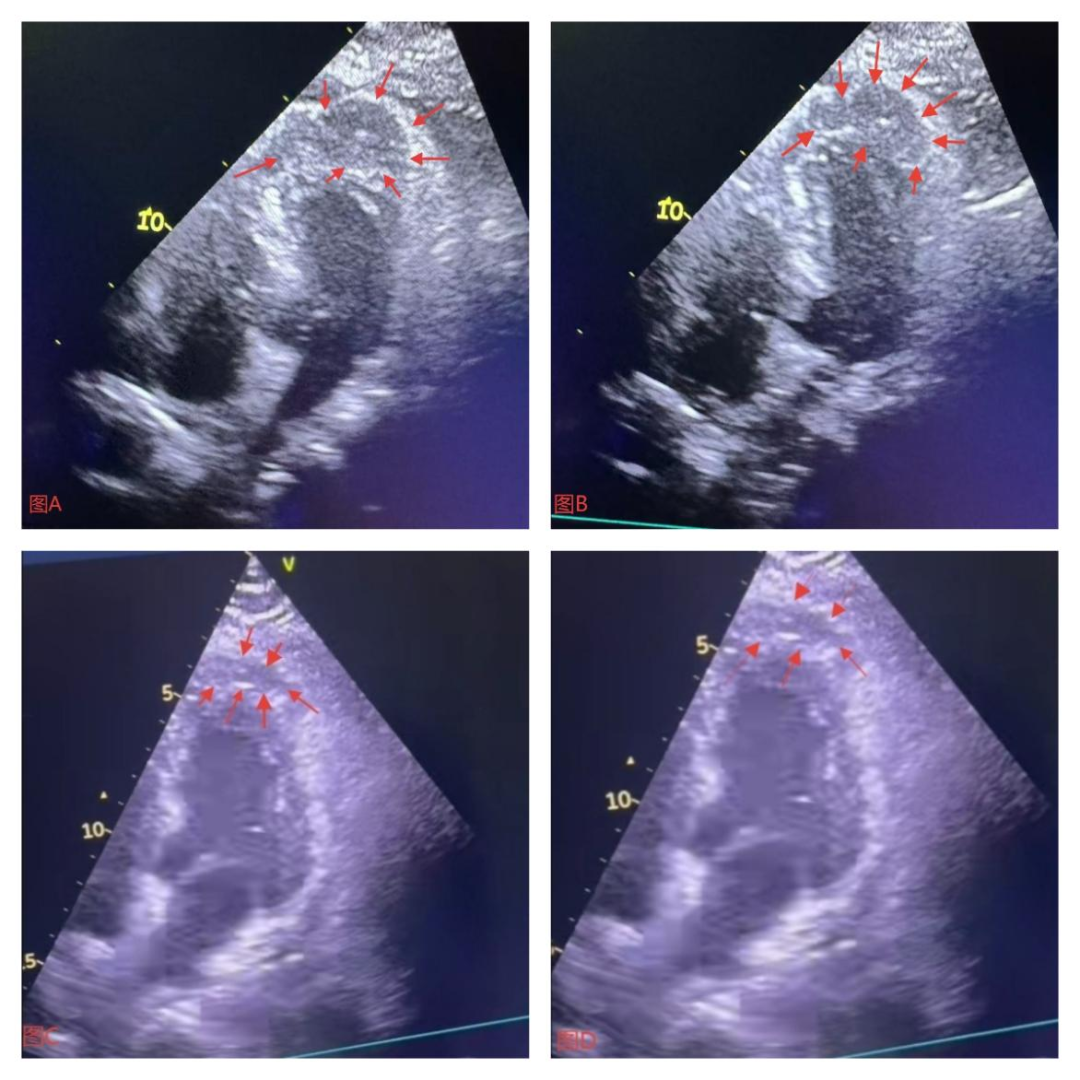

图3 图A为第二次造影发现冠脉穿孔后床旁超声检查结果,如箭头所示心尖段心外膜与心肌间低回声区;

图B为冠脉穿孔封堵后2小时床旁超声检查结果,如箭头所示心尖段心外膜与心肌间低回声区;

图C为冠脉穿孔封堵后24小时床旁超声检查结果,如箭头所示心尖段心外膜与心肌间低回声区;

图D为冠脉穿孔封堵后48小时床旁超声检查结果,如箭头所示心尖段心外膜与心肌间低回声区;

遂送美敦力6F EBU3.5指引导管至LM开口,分别送Sion blue导丝及BMW Universal II导丝至LAD远段及第二对角支分支近段,沿BMW UniversalII导丝送微导管至第二对角支分支近段,撤出导丝,经微导管用工作导丝推送3段长约2mm、3.0号可吸收缝合线至穿孔部位近端封堵,多体位造影未再有造影剂外渗(见图4),提示封堵成功,术后安返病房。术后患者症状减轻,密切观察患者生命体征及动态观察心脏超声变化,分别于术后2小时、24小时、48小时动态复查心脏超声彩超示心肌血肿逐渐吸收,血肿面积逐渐减小(见图3)。患者出院后坚持口服